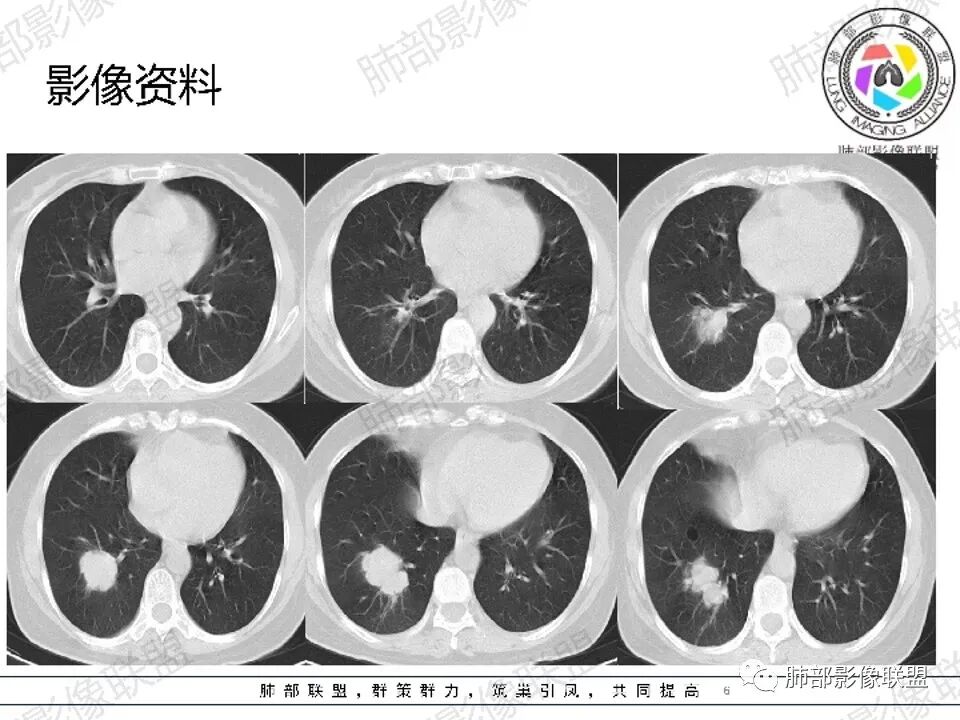

左肺门肿块,不均一强化,分叶,钙化,支气管堵塞,首先考虑直肠癌转移

必有路: 女性,中老年人,3年前直肠癌,如今体检发现右肺下叶团块,分叶,边清,无毛刺,无晕,强化不均,内部坏死,无支气管堵,无淋巴结肿大诊断:倾向恶性,转移瘤可能鉴别:原发肿瘤(神经内分泌癌>腺)建议:查肿瘤指标,尤其cea,追问原来直肠癌病理类型,活检

361度:

中年女性,既往直肠癌手术病史,现发现右肺下叶肿块,似两个结节融合。边缘膨隆,支气管阻塞,增强扫描不均匀强化,内血管影边缘模糊。考虑气道转移性肿瘤,鉴别肺原发肿瘤。

金豆 (刘权威): 右肺下叶类圆形结节,膨胀性生长,边缘清,浅分叶,轻度强化,内可见坏死,似乎坏死不太彻底,坏死边缘模糊,考虑恶性,腺癌,鉴别鳞,寡转移(既往直肠癌病史)。

空格: 中年女性,结肠术后3年,转移的高发时段。胸部无症状,有肿瘤偷袭风险。影像特点。1 感觉不是一个结节(蘑菇兄弟?),有强化的分隔,血行转移单克隆膨胀生长应该可以排除。2 病灶有沿支气管扇形分布,有沿支气管生长的可能,有结肠癌支气管内膜转移的可能   3 病灶低强化,有坏死,结肠癌转移一般强化较明显。不知道病人术后有没有放化疗,引起的低免疫状态,是否存在机会感染的可能。支气管内膜转移的发生率极低,从概率的角度。我的排序:鳞癌》隐球菌(结核)》支气管内膜转移。

必有路: 影像不像原发腺 女性鳞少,支持转移,3年前手术,必定有胸部检查,下肺,扫腹部ct也会看到,即便没有胸部ct,3年前无,现在有,小细胞不像,大细胞没那么快,原发腺,鳞,长没那么快… 除非低分化,少见的

前提排除肉芽肿病变先,影像没往这考虑

要么就是少见的肿瘤,黑色素瘤 或者 神经内分泌肿瘤 肺转移  平扫密度也比较高,不排除

所以要追问直肠肿瘤病理,上面我都写了

许慧良:

中年女性患者,右肺下叶后基底段占位性病变,

边界清楚,见分叶征,伴有纤维索条影,无毛刺,部分层面见磨玻璃晕,周边卫星灶不明显,内部密度不均匀,增强不均匀轻度强化,考虑恶性,腺癌可能,鉴别炎性肉芽肿

自信人生:

中年女,直肠癌术后病史  右肺下叶占位性肿块,浅分叶。增强后不均匀强化,内可见坏死,边缘毛刺考虑恶性,

首先转移瘤,鉴别原发肺癌

谢加平:

右肺下叶分叶状肿块,边界清,轮廓呈花瓣状,不均匀中等强化,内见多发坏死区,首选肺恶性肿块(腺Ca),既往直肠ca术后病史,与转移Ca鉴别,建议临床肺穿刺活检明确诊断!

吴婧wj:

支持恶性,转移首先考虑。其次原发,但是周围没有毛刺,很光滑,腺癌不太符合。原发放后面吧,单发,可以先做petct或全身检查排除多处转移可以切除,活检穿刺明确。边缘膨隆,坏死明显,无树丫无空洞,炎症不是太符合

3年前直肠癌手术,最起码当时不明显

△外后基底段支气管应该堵了,深分叶,

△坏死边界不清,支持恶性。

就肺部病灶本身而言,深分叶,近端支气管显示欠佳,双侧对比还是符合堵塞,强化也支持恶性特点,那就是良性肿瘤不支持,如果要考虑良性,就是特异性感染了。